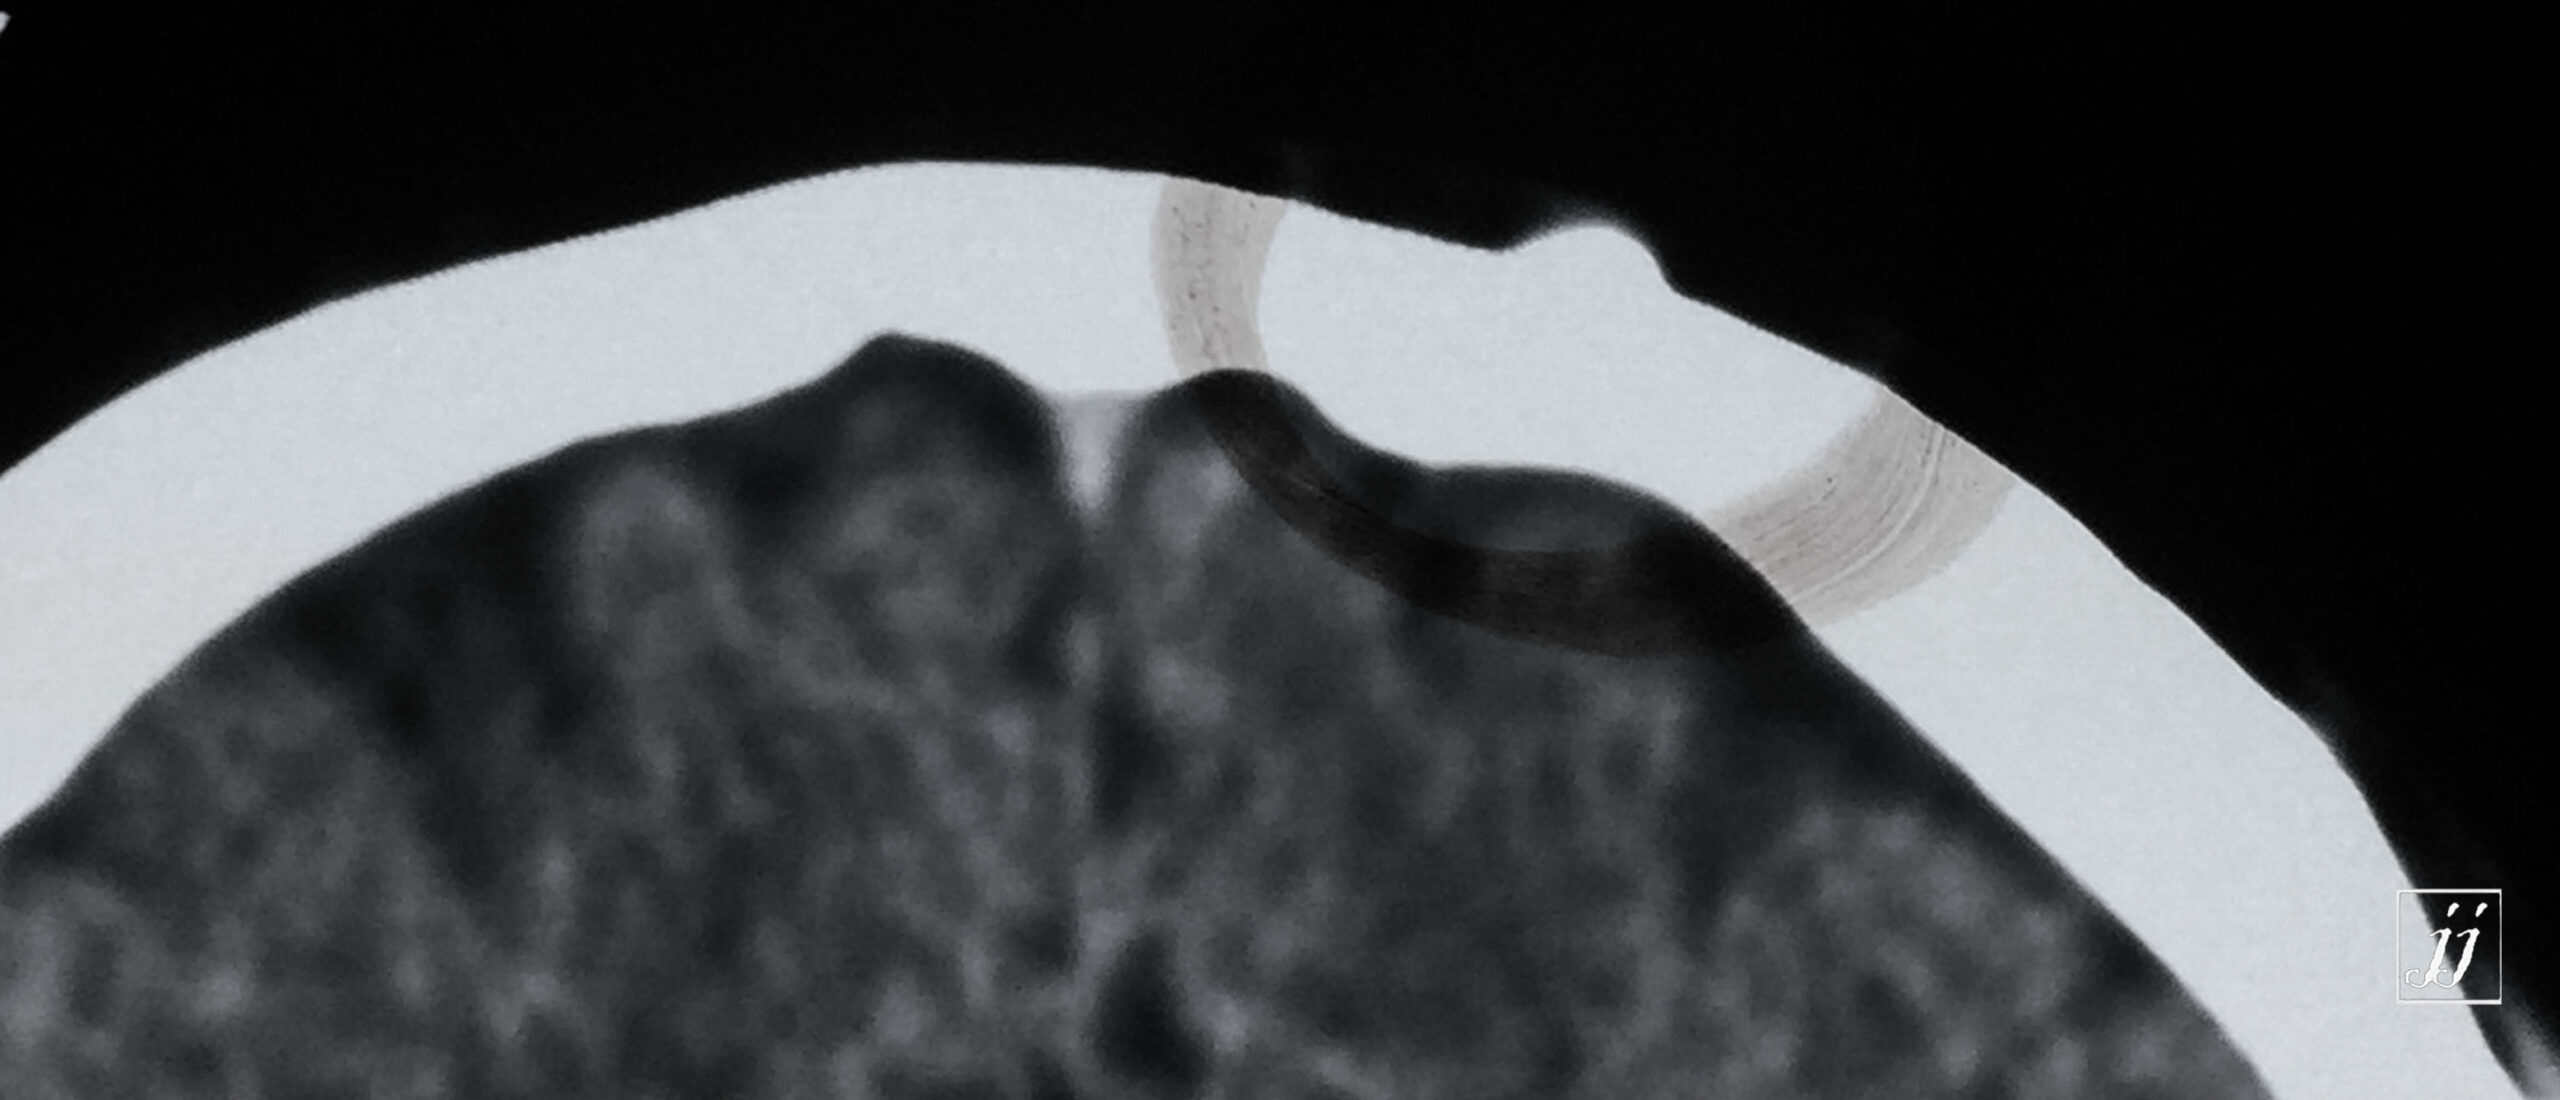

Brain- small osteoma (9)